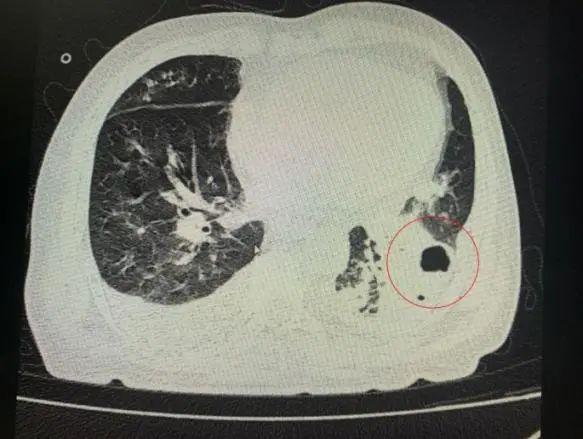

番禺院區(qū)呼吸內(nèi)科何夢璋主任接診后,對鐘叔進(jìn)行詳細(xì)檢查。此時,鐘叔的病情已經(jīng)十分危急,由于不能自主呼吸,他帶上了呼吸機(jī)輔助呼吸調(diào)節(jié)。看到鐘叔胸片時,醫(yī)護(hù)人員頭皮也一陣發(fā)麻,胸部CT可見雙肺多發(fā)的炎癥浸潤、雙肺多發(fā)空洞。通俗來說,鐘叔的肺部已經(jīng)被病原體蠶食,啃出個大小各異的洞!可怕的是,這種病變對肺功能的破壞是性、不可恢復(fù)的。根據(jù)鐘叔病史以及胸部CT結(jié)果,終診斷為“吸入性肺膿腫”。

鐘叔的肺部被病原體蠶食,啃出個大小各異的洞。